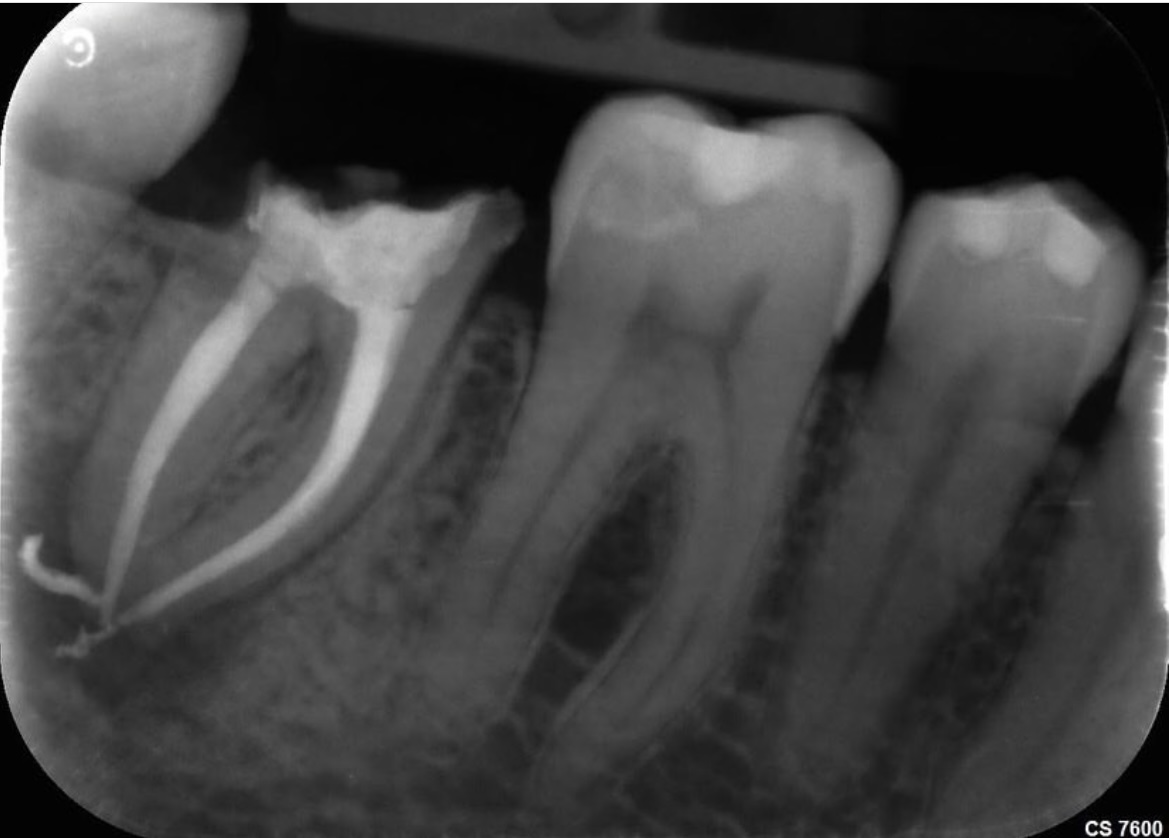

3. L’examen microscopique de la dent et l’imagerie médicale complètent si besoin le diagnostic clinique, notamment en cas d’obturation préalable sur une dévitalisation imparfaite. Nous sommes équipés d’un matériel haut-de-gamme permettant des diagnostics très précis (radiographie, Cône Beam, microscope, …) ;

• vérification de la qualité de l’obturation par radiographie haute définition.

Une dévitalisation se traduit par la suppression des tissus enflammés/infectés, en nettoyant les canaux situés à l’intérieur de la dent de toutes les bactéries et les débris organiques. Une fois désinfectés, ces canaux sont remplis d’un matériau biocompatible qui va assurer leur étanchéité parfaite et empêcher une nouvelle infection. La dévitalisation ne donne pas une dent “morte”, elle la rend simplement insensible. Il faut donc veiller à conserver sa vitalité, avec notamment un parodonte sain.